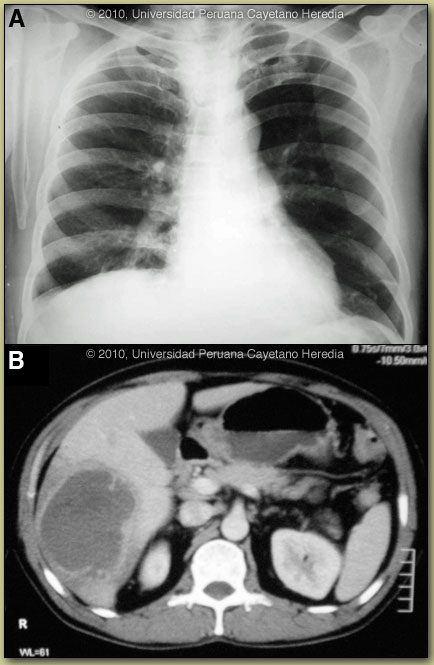

| Diagnosis: Liver abscess due to Entamoeba histolytica. |

E. histolytica is a single celled intestinal protozoan parasite that is transmitted from human to human via the fecal-oral route. Infectious cysts are excreted into the environment and are ingested by new human hosts where only a small proportion of the cysts will excyst to become tissue invasive. Thus, 90% of infections result in asymptomatic disease and up to 10% of the world’s population may be infected. The 10% of infections that are invasive mostly cause dysentery and colitis and in only 1% of total infections is there extra-intestinal dissemination, mostly to liver and brain. Direct extension of amebic liver abscesses (ALA) may result in pleural and pericardial infection and direct extension from the rectum may cause perianal cutaneous disease. The non-pathogenic E. dispar and E. moshkovskii, which are 10 times more common than E. histolytica in stool specimens, have cysts which appear identical by microscopy but never become invasive. Other non-pathogenic ameba, which are morphologically distinct include: E. polecki, E. hartmanni, and E. coli. Typical presentation of ALA in Perú includes an insidious onset over several weeks, fever in 90%, weight loss in about half, concomitant diarrhea in about a third, abdominal pain in over 90%, tender hepatomegaly in 30-50%, and jaundice in less than half. There is a male predominance and most infections are in 20-50 year olds. General laboratory findings include an elevated white count with left shift in almost all patients, mildly elevated transaminases and alkaline phosphatase, and sometimes mildly elevated bilirubin. As most patients at the time of diagnosis of ALA do not have a concurrent intestinal infection with Entamoeba histolytica, stool examination is positive in less than 10% of cases. The noninvasive diagnosis of ALA is challenging. Serology is positive in approximately 90-100% of invasive amebiasis cases either intestinal or extra-intestinal but only become positive by the second week of illness. ELISA is currently the most common commercially available antibody detection test used. Anti-amebic antibodies are not present in non-invasive or asymptomatic infection and are not present in E. dispar. Using a commercial kit, the Gal/GalNAc lectin antigen of E. histolytica can be detected in serum in 96% of ALA cases and is present in abscess fluid about 50% of the time. As with stool microscopy, antigen is infrequently present in stool in ALA cases [J Clin Microbiol. 2000 Sep;38(9):3235-9]. However, patients with amebic intestinal infection with another cause for a liver lesion may also have serum antigen present though this is not a frequent occurrence. Detection of antigen in the abscess fluid, however, is a definitive finding. Serum antigen detection is significantly affected by treatment with a negative test result after one week of treatment in 82% of patients; the test should be ordered before starting antibiotics or soon thereafter. A recent study has shown that when both tests are performed, E. histolytica DNA can be detected either in urine or saliva in 97% (92/95) of ALA cases by real-time PCR [J Clin Microbiol. 2010 Aug;48(8):2798-801]. DNA was present in serum in only 49% of ALA cases. Imaging typically shows an elevated R hemi-diaphragm, as in our case. On ultrasound or CT scan a single abscess is found in 90% of cases. As spread from the intestine occurs via the portal circulation it is thought that initial small multiple abscesses often coalesce into one large abscess within a short period of time. Differential diagnosis includes pyogenic liver abscess, which is much more common in older individuals but usually is identical on ultrasound or CT scan and presents with a similar clinical picture. Patients with echinococcal cysts usually have distinctly different CT scan appearances [see Gorgas Case 2003-03] and are rarely febrile, ill-appearing or toxic. Hydatid cysts often are complex with daughter cysts and distinct internal septations. Some hepatomas may also appear similar on CT scan. Treatment is with either metronidazole (10 days) or tinidazole (5 days), plus a lumen active agent such as paromomycin or diodoquinol. Oral therapy is the preferred route. Therapeutic aspiration of an amebic abscess is not usually necessary. Indications include no resolution of fever by Day 4-5 of anti-protozoal therapy, large abscess (>10 cm), or left lobe location (danger of pericardial invasion). Response to therapy is monitored by resolution of fever. The hepatic cavity created by the abscess may remain detectable by ultrasound or CT for more than 6-12 months and is not an indicator of treatment success or failure.Our patient remained febrile after 4 days of combined antibiotic and anti-amebic therapy and with a 9 cm cyst, aspiration and drainage for both diagnostic confirmation and therapeutic effect was undertaken. His fever then resolved within 24 hours of the procedure. |